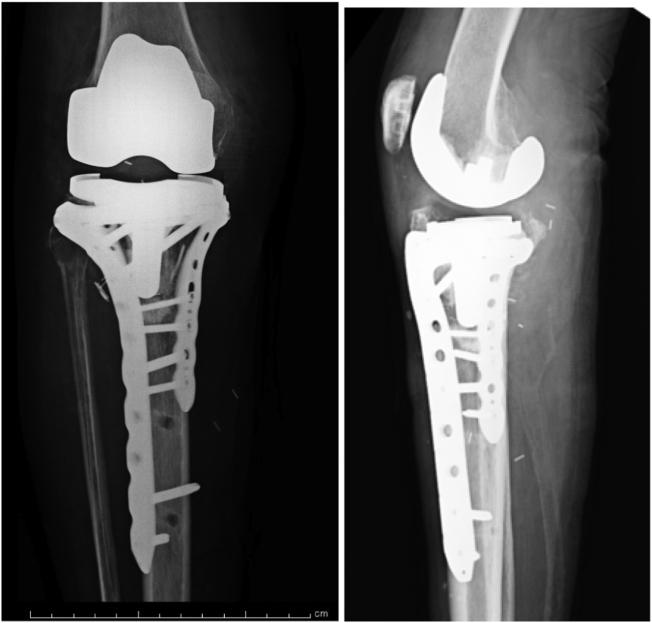

We present the case of a 79-year-old woman who presented at our center with a periprosthetic tibial fracture with a popliteal artery injury after total knee arthroplasty. Anastomosis of the popliteal artery was performed on the day of injury, and was later treated by open reduction and internal fixation. The patient was able to walk 3 months after injury. The present case was difficult to treat because of the arterial injury associated with periprosthetic fracture. Although revision of the implant was considered, open reduction and internal fixation was selected because of the severity of soft-tissue damage. The mechanism of injury is not uncommon, and it is expected that similar fractures will become more prevalent in the future as the number of knee replacement surgeries increases.

我们报告了一例79岁女性患者的病例,该患者在全膝关节置换术后因假体周围胫骨骨折合并腘动脉损伤前来我院就诊。受伤当天进行了腘动脉吻合术,随后接受了切开复位内固定治疗。患者受伤后3个月能够行走。由于假体周围骨折合并动脉损伤,本病例治疗困难。尽管考虑了翻修植入物,但由于软组织损伤严重,选择了切开复位内固定。这种损伤机制并不罕见,预计随着膝关节置换手术数量的增加,未来类似骨折将变得更加普遍。